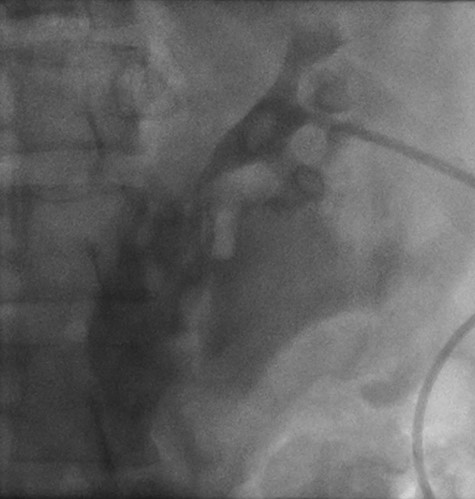

Fetal HR was measured at 135 bpm. Chest X-ray revealed a small apical pneumothorax and a fractured right clavicle. She was taken to the computed tomography (CT) scanner where CT-CAP with contrast revealed a Grade 2 liver laceration, Grade 3 splenic laceration and bilateral Grade 4 kidney injuries with extravasation of contrast on the renal delay, suggestive of urine extravasation. No pelvic fracture was found on imaging (Figs 1 and 2).

Cystoscopy with retrograde pyelogram was performed by the urology team and this showed total disruption of the UPJ bilaterally with extravasation of contrast (Figs 3 and 4). She underwent bilateral interventional radiology nephrostomy tube placement. The definitive repair was planned for after pregnancy, but she required tube changes every 6 weeks. There was no fetal distress during her stay. She recovered well and was discharged after 5 days.